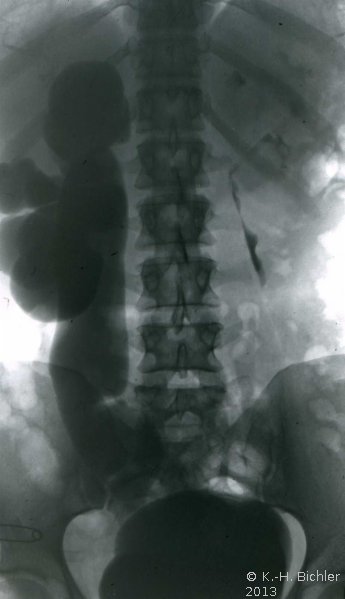

Die Ureterozele kann auch trotz Komplikationen (Harnsteinbildung) und schwersterster Abflussbehinderung lange Zeit unerkannt bleiben (rezidivierende Harnwegsinfekte) wie bei dieser Erwachsenen mit sekundärem Megaureter bei steintragender Ureterozele rechts und rezidivierendem Harnwegsinfekt (Abbildung 3) (

KasuistikKasuistikBei dieser 54jährigen Frau fand sich ein sekundär-obstruktiver Megaureter bei Ureterozele mit Harnsteinbildung. Jahrelang rezidivierende Harnwegsinfekte ohne entsprechende Abklärung. Therapie: Schlitzung der Ureterozele und Harnsteinentfernung (s. Abbildung 3).).